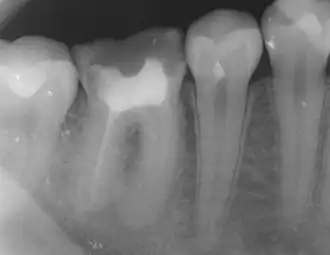

Tooth #30, the lower right first molar, with incomplete endodontic therapy: the mesial roots were left untreated, as can be evidences by the lack of gutta percha in the canals. This tooth requires retreatment to prevent a future infection from the non-treated canals.